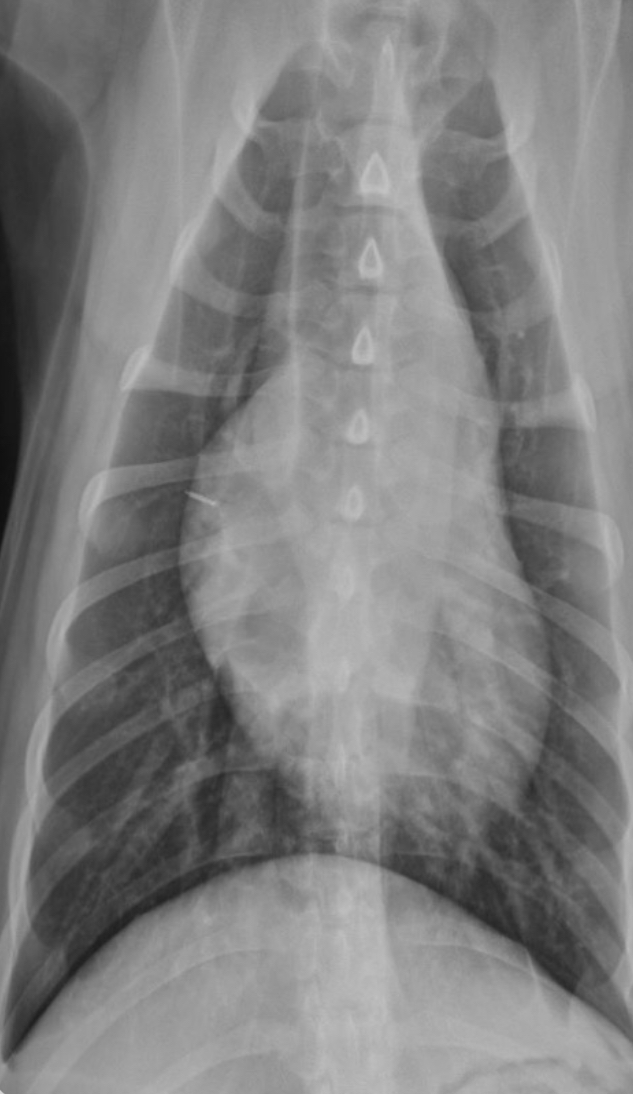

3 features of LVE VD

-elongation of cardiac silhouette

-deviation of apex to the left

-bulge at 3-5 o’clock

What part of the heart is enlarged?

LVE

2 features of RVE on VD

-bulge 5-9 o’clock

-reverse D

What part of the heart is enlarged

RVE